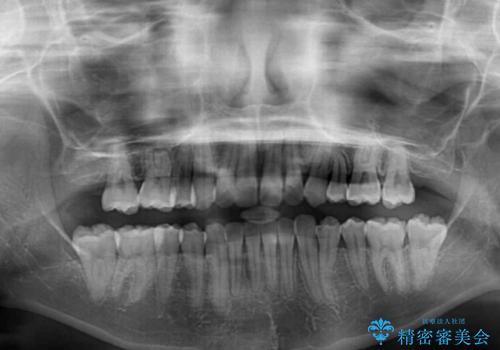

- 口元の突出感を気にして来院された患者様です。

左右ともに上顎奥歯が外を向き、下顎奥歯が内側に倒れているシザーズバイトであったため、補助装置により改善することとしました。

上下の咬み合わせは、下顎に対して上顎が相対的に前方にあったため、奥歯のシザーズバイト改善後に上顎左右第一小臼歯2本を抜歯し、上顎前突を改善していくこととしました。